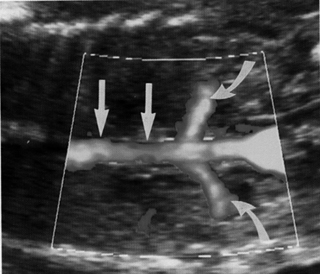

| Εικόνα 1. Φυσιολογική απεικόνιση των νεφρών. | Εικόνα 2. Φυσιολογική

απεικόνιση νεφρικών αρτηριών. |

Εικόνα 3. Απουσία νεφρικών αρτηριών. |

Υπερηχογραφικά, η κατάσταση αυτή γίνεται αντιληπτή με πλήρη απουσία αμνιακού

υγρού και μη ορατή ουροδόχο κύστη. Το έγχρωμο Doppler βοηθά στη διάγνωση -δεν

απεικονίζονται οι νεφρικές αρτηρίες και επιβεβαιώνεται η απουσία νεφρών (εικόνες

2, 3).